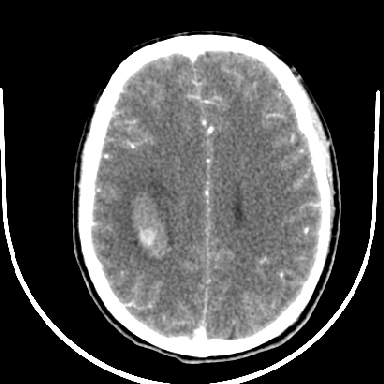

标题: CT6056:脑出血(血管畸形?)

m 40突发头痛左侧偏瘫3小时

考虑高血压性脑出血,依据:

1是高血压性脑出血的好发部位,形态呈肾形,是高血压性脑出血的常见形状

2增强时占位效应加重了,考虑出血还没有停止

3病灶周围水肿不是太厉害,一般肿瘤出血水肿多非常明显

4病灶周围的‘软组织’影没有明显的强化

5至于脑血管畸形引起的出血,暂时没有看到明显的畸形血管影,也不太支持

支持右侧基底节脑出血

右侧基底节区脑出血.

支持右侧基底节区(主要为外囊区)原发性脑出血。

另附部分资料:“血液溢出血管外形成血肿,其内含有大量血红蛋白、血浆白蛋白,球蛋白,因这些蛋白对x线的吸收系数高于脑质,故ct呈现高密度阴影,ct值达40~90h,最初高密度灶呈非均匀一致性,中心密度更高,新鲜出血灶边缘不清。基底节区血肿多为“肾”型,内侧凹陷,外侧膨隆,因外侧裂阻力较小,故向外凸,其它部位血肿多呈尖圆形或不规则形”

术中抽出40ml陈旧血液,血肿底部似见一条索血管影